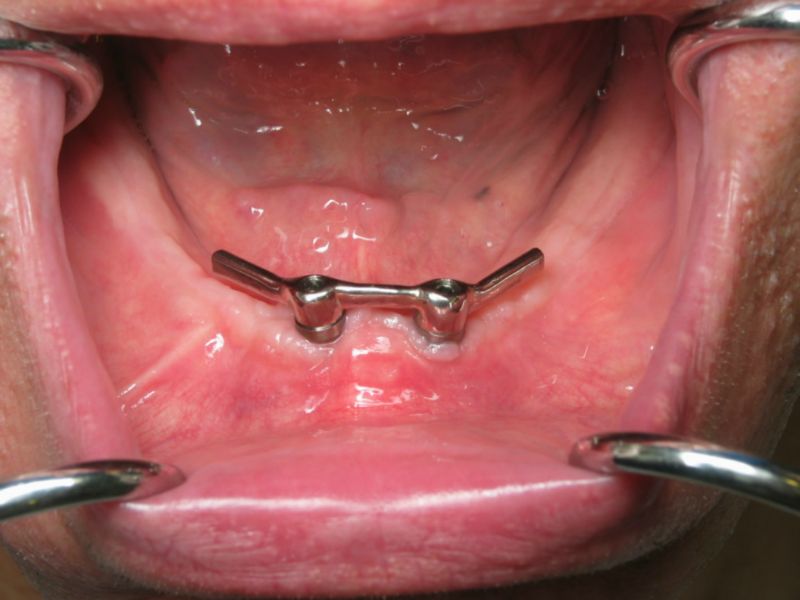

- Boutons-pression à la mandibule

A la mandibule

Il ressort de l’analyse des publications que la technique des boutons-pression a été mal perçue dans les premières années d’application des techniques implantaires du fait de systèmes peu efficaces et par analogie aux traitements par boutons-pression supra-radiculaires sur des racines dentaires résiduelles qui étaient parfois précaires et d’ancrage médiocre.

La revue de la littérature scientifique montre que la technique de boutons-pression est à présent considérée comme une option de choix quand il s’agit d’améliorer la rétention d’une prothèse amovible complète à la mandibule, avec comme principaux avantages la simplicité d’exécution et la maintenance réduite par rapport aux barres.